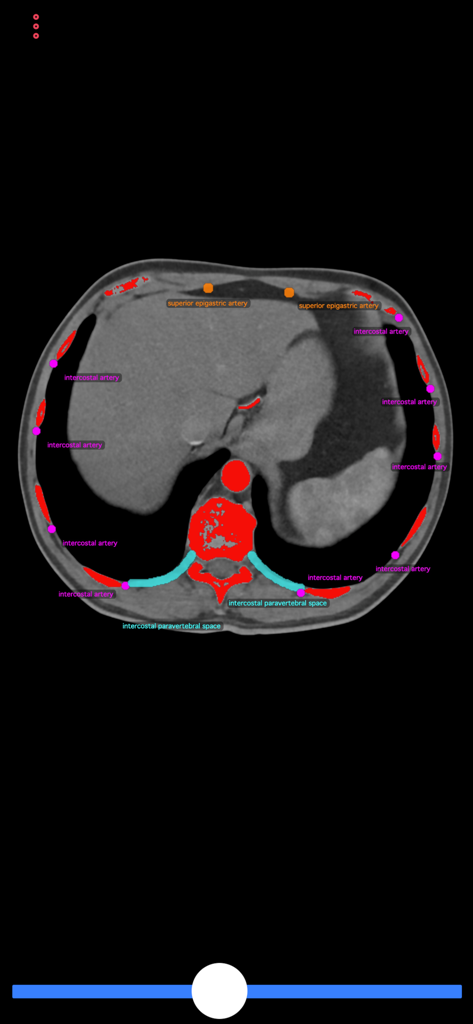

Sección transversal de escaneo TC con etiquetas anatómicas para la guía del procedimiento de biopsia

Sección transversal de escaneo TC en la aplicación Guía de Biopsia con estructuras anatómicas etiquetadas como el colon y las arterias

Identifica Puntos de Referencia Críticos

Minimiza el riesgo del procedimiento visualizando órganos vitales, vasos principales y nervios dentro de secciones transversales detalladas para garantizar una biopsia segura en todo momento.

Esta aplicación consiste en TC (tomografía computarizada) de cuerpo, que demuestra posibles sitios de punción y estructuras anatómicas a evitar durante las intervenciones. El usuario puede desplazarse por las secciones transversales de la TC para encontrar el acceso de punción ideal. Esta aplicación puede guiar a radiólogos intervencionistas y generales, pero también a médicos de atención primaria o a cualquier médico de diagnóstico para realizar una biopsia segura o la colocación de un catéter de drenaje sin lesionar a los pacientes.